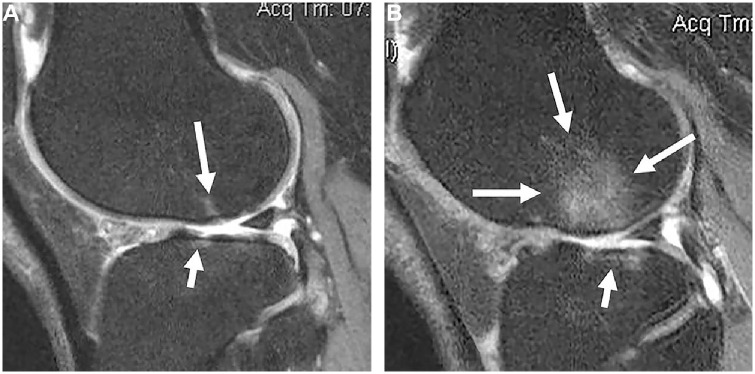

Abstract Image